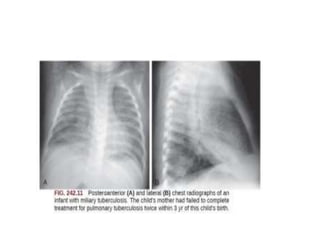

C/F:Miliary disease

•Lympho-haematogenous dissemination to spleen,

liver, lung, lymph nodes, skin, bones,

joints,kidneys,peritoneum, pericardium and

meninges

• Common in immune compromised/malnourished

• Sxs : pt gravely ill with Sx complex of TB,

• Sns : TST non reactive in 40% of pts,

hepatosplenomegaley , emaciation, Sns of

meningitis, peritonitis etc

• Resolution is slow with Tx , steroids for Sxic relief

• Excellent prognosis with early Tx